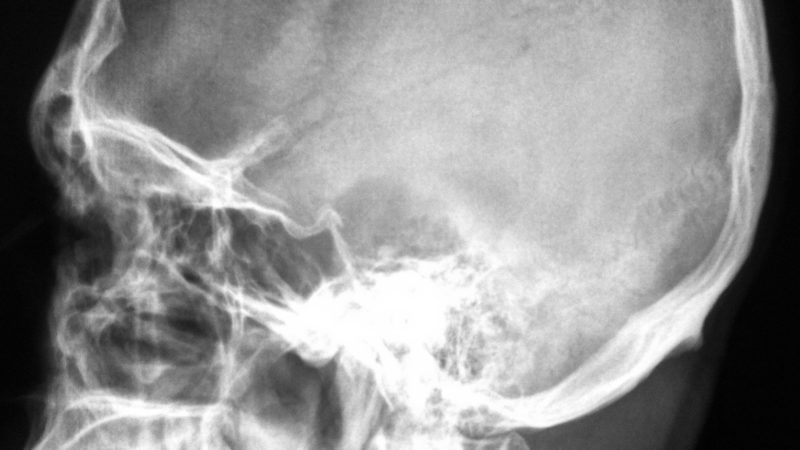

Articles Skull Fractures Article Topic: Skull fractures Author name: Zaid Sayegh Edited by: Philip Sweidan, Ethar Hazaimeh Keywords: ...